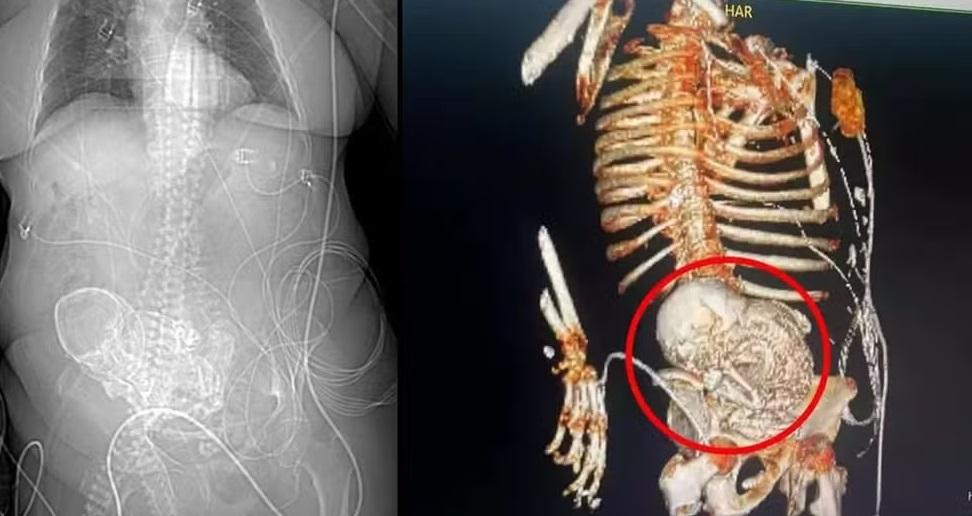

feto calcificado

Legenda: A mulher descobriu o feto após 56 anos

Foto: Reprodução

Uma idosa de 81 anos morreu, no último dia 15, no Mato Grosso do Sul, após passar por uma cirurgia para retirada de um feto calcificado que ela carregou no corpo por mais de cinco décadas.

A mulher deu entrada no Hospital Regional de Ponta Porã, no Mato Grosso do Sul, no dia 14, com uma infecção grave e fortes dores abdominais. Depois da realização de uma tomografia 3D, a equipe médica identificou um feto calcificado na região do abdômen da idosa.